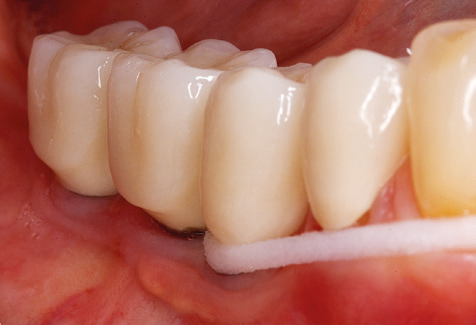

A 52-year-old patient presented in our clinic for the first time in 2004 following tooth loss in the third quadrant, expressing a desire for a new prosthetic restoration. Periodontal and radiological diagnostics revealed the need for extensive periodontological treatment. In addition, teeth 48, 28 and 27 were attributed a very poor prognosis and were subsequently extracted (Fig. 1). Following the successfully completed, systematic periodontological treatment, a fixed dental implant was inserted with the introduction of five implants in tooth regions 35, 36, 37, 46 and 47. Prosthetic treatment of the natural teeth was effected with veneered zirconium dioxide ceramic crowns; the implants were composed of two-piece, individual zirconium dioxide abutments and similarly veneered crowns made of a zirconium dioxide ceramic (Cercon base colored, Dentsply Sirona Lab). Definitive insertion of the prosthetic restoration occurred in 2005.

Due to the presence of periodontal disease, SPT was performed every three months in the first years following the insertion. The patient demonstrated a high degree of motivation and good compliance. The pocket depths recorded annually revealed a stable periodontal situation with a BOP index of below five per cent. On the basis of the stable periodontal situation and good cooperation on the patient’s part, the recall interval was extended to every six months as of the sixth year of the prosthetic function phase. Following the change in the recall interval, the respective annual documentation of the periodontal status continued to reveal a stable periodontal situation with no increase in the pocket depths and a BOP index below five per cent (Fig. 2a and b).